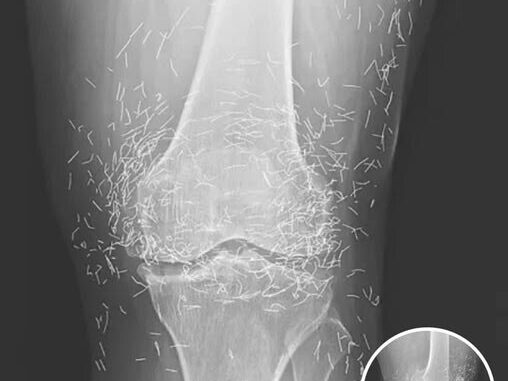

A routine scan in South Korea revealed a 65-year-old woman’s knee was filled with hundreds of tiny gold needles. What she thought was ordinary osteoarthritis pain—stiffness, swelling, and cartilage wear—turned out to be far more unusual.

She had tried standard treatments like painkillers and anti-inflammatories with little relief, so she turned to acupuncture. While generally safe, prolonged or improper techniques can leave retained needles, which may cause inflammation, tissue damage, or infection over time.